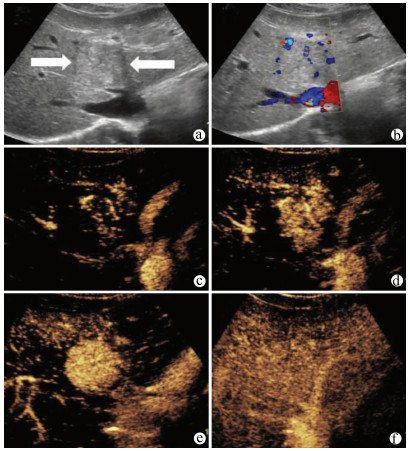

肝病超声诊断指南

中华医学会超声医学分会, 中国研究型医院学会肿瘤介入专业委员会, 国家卫生和健康委员会能力建设和继续教育中心超声医学专家委员会

2021, 37(8): 1770-1785. DOI: 10.3969/j.issn.1001-5256.2021.08.007

超声检查无创、实时、价廉,无辐射、便于反复进行,是最常用的肝脏影像学检查方法。近年来,超声检查新技术如超声造影、弹性成像发展迅速,可有效鉴别肝内占位性病变性质、评估肝纤维化和门静脉高压程度以及监测肝病治疗效果,在临床肝病及其介入治疗中发挥重要诊断价值。本指南规范了肝病多模态超声技术(灰阶超声、彩色多普勒超声、超声造影、弹性超声)检查的仪器调置、患者准备及医生检查方法;对肝脏弥漫性病变(炎性病变、纤维化、硬化)、多种占位性病变及肝病介入操作的多模态超声技术诊断标准进行了定义和规范,同时推荐了超声监测周期及肝脏疾病超声诊断报告书写规范。